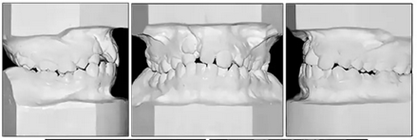

咬合關(guān)系:右側(cè)磨牙有II類關(guān)系傾向,尖牙關(guān)系II類;左側(cè)磨牙關(guān)系完全II類,尖牙關(guān)系I類。上頜雙側(cè)反合,中線稍有偏離。覆合、覆蓋減少。上頜中切牙向腭裂側(cè)旋轉(zhuǎn),上頜右側(cè)尖牙頰側(cè)異位萌出,雙側(cè)乳尖牙仍存在?;颊呱项M弓嚴重擁擠(擁擠度約10mm),下頜弓輕度擁擠4mm(擁擠度約4mm)(圖1 ;圖2)。牙周檢查良好。